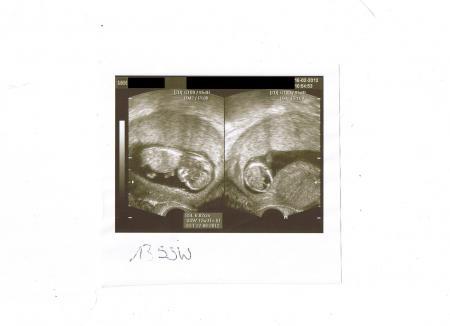

Huhu Zusammen! Hab's gestern nimmer ganz geschafft, weil mein großer so schlecht geschlafen hatte und ich das mit dem einscannen der Bildchen net so schnell hin bekam. Beim FA war alles super. Baby hatte die Beinchen erst überkreuzt und die Händchen am Kopf. beim Vermessen hat's dann kräftig gestrampelt, hat ihm wohl nicht so ganz gepasst. Mein Hb ist bei 11,5 bin ich soweit ebenfalls zufrieden damit. Hoffe das er in dieser Schwangerschaft nicht wieder so weit absinkt. Zugenommen hab ich nur erstaunlich wenige 800gr. freut mich auch mal. :-) Bei meinem Sohn hab ich 15kg in der Schwangerschaft zugenommen, mal sehen wieviel es dieses mal noch werden. Unser Sohn inklusive Papa, waren super begeistert von dem Zwerg und unser Kleiner hat das US-Bildchen erstmal nicht aus der Hand gegeben mit dem Baby *g* In vier Wochen am 15.3. ist dann der nächste Termin. Bildchen hänge ich an. Liebe Grüße Traeummaus

dankeschön! Achso, der Bauchzwerg is schon 6cm groß :-) hatte ich ganz vergessen zu schreiben. hihi